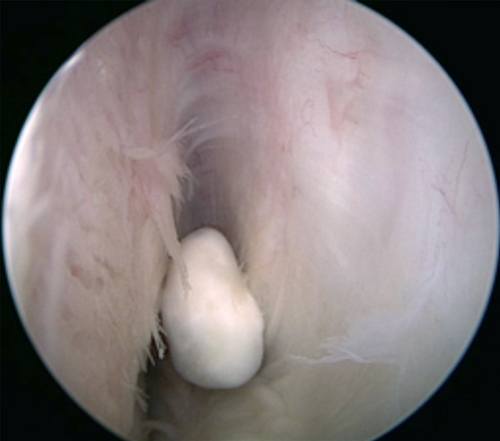

Et corpus liberum fjernes i de fleste tilfeller ved kikkhullskirurgi (artroskopi). Dette forhindrer ytterligere skade på leddet.

Corpus liberum Leddmus / løst fragment i leddet